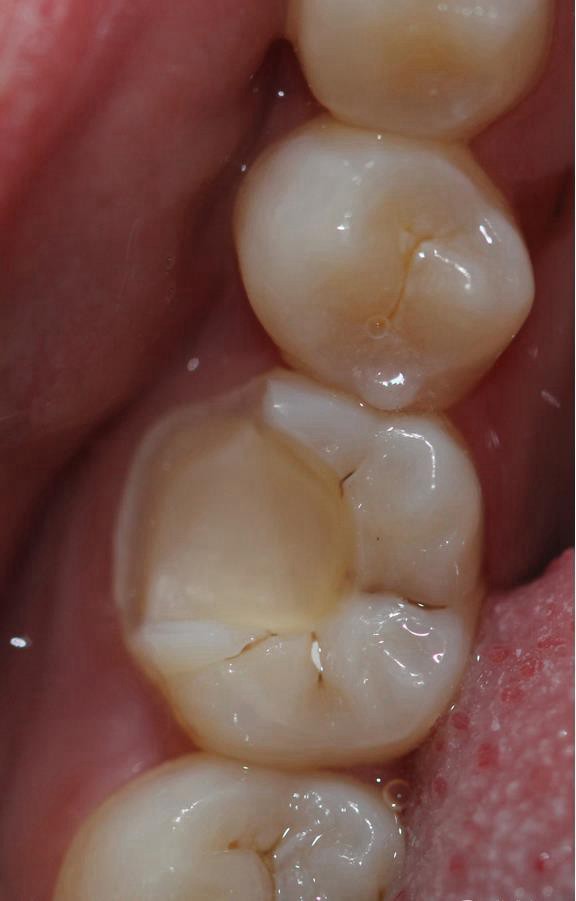

根管治療完之后,樹脂墊底,不需要加樁 不管你是做樹脂嵌體還是瓷嵌體。

牙體根充完制備 ,剩余的牙體組織最小的厚度為2mm。

粘接 去除多余的粘結(jié)劑 進行光照 調(diào)HE 一周后進行拋光

粘接后X線片

復診拋光 很容易看到邊緣線,原因是主要有兩個:一-瓷塊選擇不準確,目前我們單位瓷塊顏色單一。二- 粘結(jié)劑,選擇和牙體顏色不一致的。我選擇的偏白,所以邊緣白線較明顯。